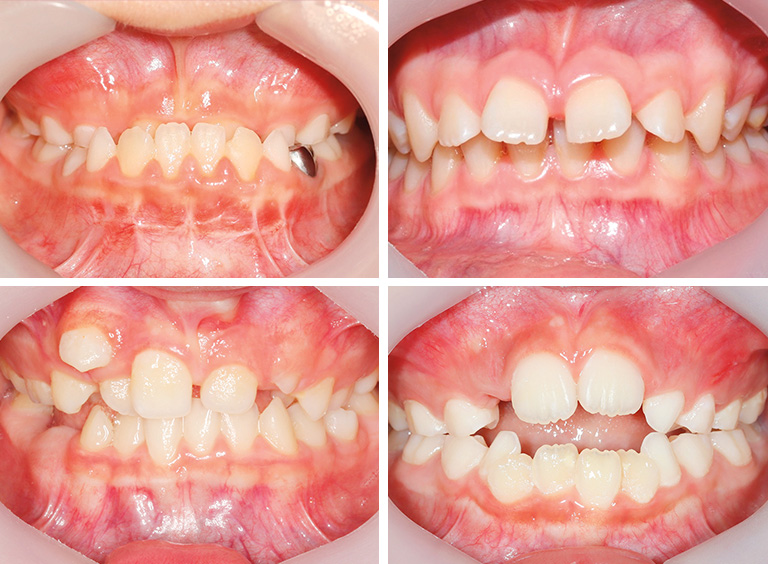

소아청소년기 부정교합의 여러 형태

많은 부모가 “교정은 영구치가 다 난 뒤에 하는 것 아닌가요?”라고 묻지만, 모든 아이에게 같은 시기가 적용되는 것은 아니다. 부정교합의 원인과 유형에 따라 치료 시작 시점이 다르며, 너무 이르거나 늦은 치료 모두 바람직하지 않다. 예를 들면 다음과 같다.

주걱턱 (앞니가 반대로 물리는 경우)

위턱 성장이 부족하면 앞니가 반대로 물리는데, 7세 이후 가능한 빨리 치료하는 것이 바람직

무턱 (아래턱 성장이 부족한 경우)

최대 성장기 직전 치료가 효과적. 보통 남아는 12세, 여아는 11세 전후가 적당